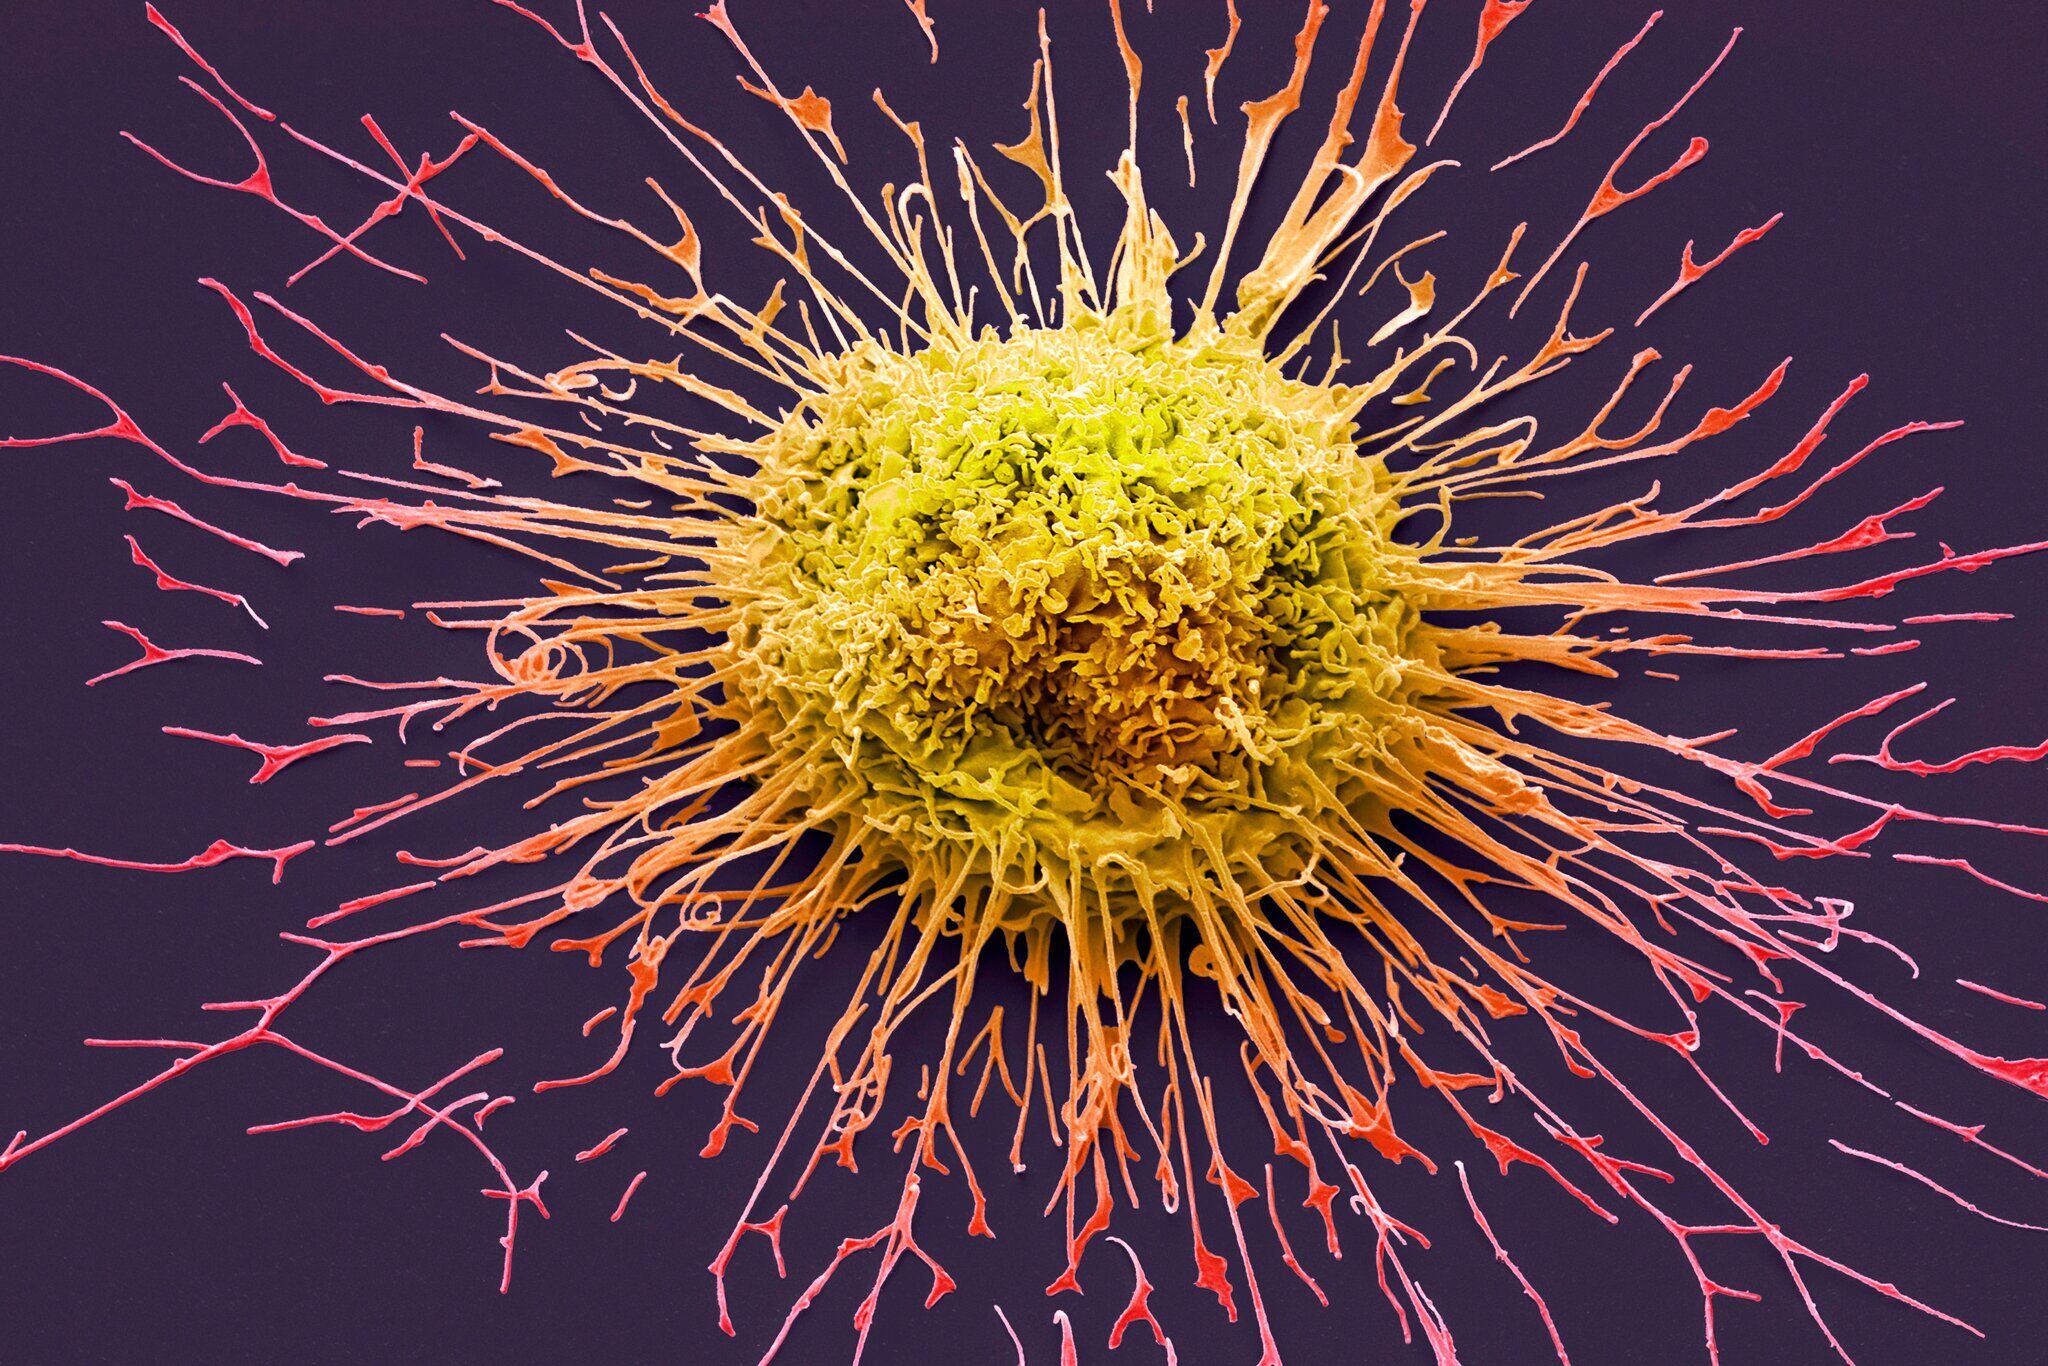

Cuando una persona deja de fumar, a las horas inclusive, empieza a recuperar el gusto y el olfato (Steve Gschmeissner/Science Source)

Cuando una persona deja de fumar, a las horas inclusive, empieza a recuperar el gusto y el olfato (Steve Gschmeissner/Science Source)

Tras una década sin fumar, el riesgo de muerte por cáncer de pulmón se va a haber reducido a la mitad, en comparación con un fumador. Según la organización benéfica Cancer Research, cuando se fuma, los cigarrillos liberan más de 5.000 sustancias químicas diferentes.

El tabaquismo también influye en otros tipos de cáncer: los expertos creen que fumar provoca al menos 15 tipos de cáncer. Puede ser la causa del cáncer de boca y garganta, recto, hígado y páncreas, por nombrar algunos.

Ross, experta en temas de tabaquismo, afirmó: “El riesgo de sufrir un ataque al corazón se reduce gradualmente, así como el riesgo de padecer todo tipo de cánceres, no sólo el de pulmón. El tabaquismo puede desencadenar todo tipo de cánceres”.

Y continuó: “No hay una regla fija de que después de diez años sin fumar el riesgo de cáncer haya desaparecido, porque depende de cuánto se haya fumado antes y de qué otras afecciones se tengan”.